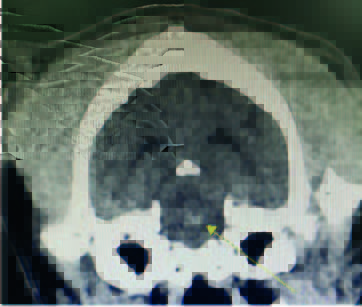

This case study involves a 5-monthsold, intact male Golden Retriever dog presented with tetraparesis, seizure and comatose by a car accident 5 days ago. Physical examination presented unconsciousness, tetraparesis, tachypnea, right temporomandibular joint (TMJ) luxated and crepitus of left humerus. Neurological examination was localized to cerebral cortex and brain stem lesions. The Modified Glasgow Coma Scale (MGCS) was 3. Laboratory tests revealed anemia of 23.1% (reference range, 35-45%), leukocytosis of 19.09 x 103/μL (reference range, 5-14.1 x 103/μL). Radiography was presented to skull fracture, lung hemorrhage (Figure 1) and left humerus fracture (Figure 2).

CT scan of skull is preferred for evaluate bone fractures and identify areas of acute hemorrhage or edema. CT scan showed multiple sites of skull fractures, right maxilla, both frontal, right zygomatic, right caudal mandible, right caudal zygomatic, right temporal, left occipital bone (Figure 3) and patchy small area of hyper-attenuation at the cranial of midbrain in pre-contrast study (Figure 4), no detectable mass effect, hypo-attenuated of large edematous parenchyma in the brain, right temporomandibular joint is displacement (Figure 5) and left tympanic bulla shows partial ventral fluid-filled.

CT skull presented to multiple skull fractures, brain edema, midbrain hemorrhage and right TMJ luxation.